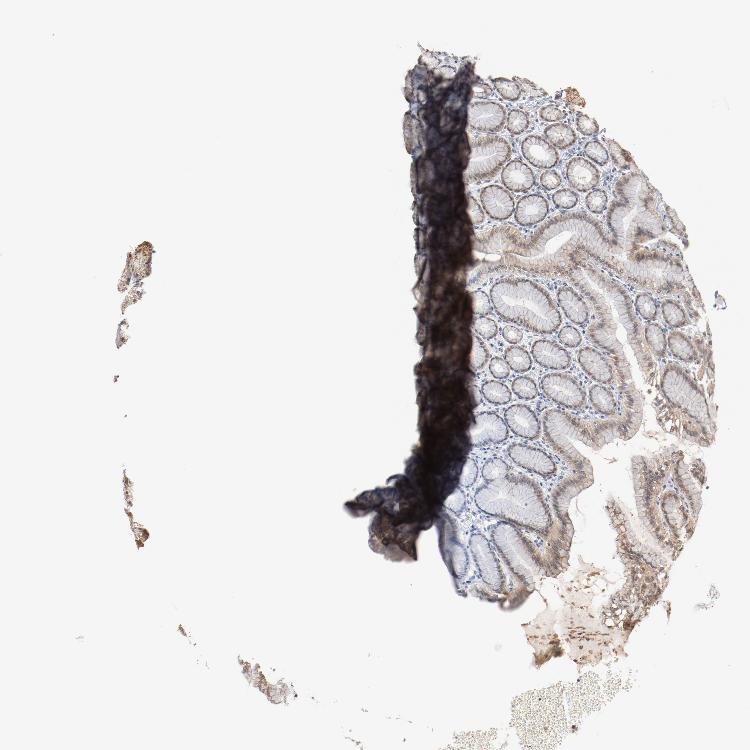

STOMACH 1 - Antibody stainingi

Antibody staining in the annotated cell types in the current human tissue is reported as not detected, low, medium, or high, based on conventional immunohistochemistry profiling in selected tissues. This score is based on the combination of the staining intensity and fraction of stained cells.

Each image is clickable and will lead to virtual microscopy that enables deeper exploration of all samples and also displays staining intensity scores, fraction scores and subcellular localization as well as patient and tissue information for each sample.

Antibody HPA003725

Glandular cells Medium